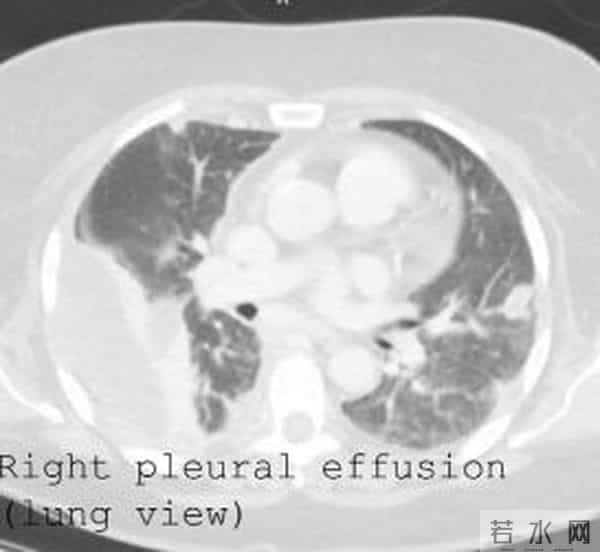

更值得关注的是,在住院期间的复查中,患者的肺结节逐渐好转,胸腔积液也仅有少量复发,这提示肺结节可能确实由感染引起,但胸腔积液的 “元凶” 却是这个异位的输卵管组织。3 个月后,患者复查胸部CT,胸腔积液和肺结节已完全消失(图3),无需进一步治疗,只需定期随访即可。

图3 3个月后肺部病灶完全消失